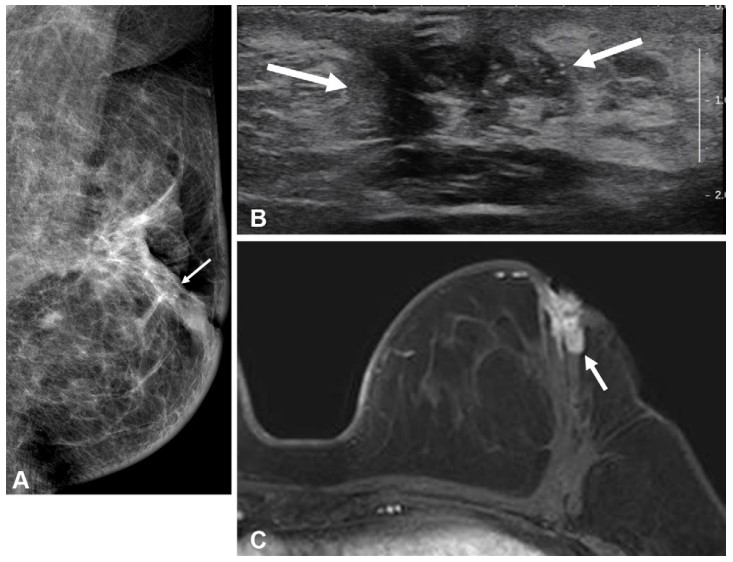

[자료1] 수술 전 MRI 검사를 시행하지 않은 50세 이하 환자의 수술 2년 후 유방 영상 검사 결과. 동측 유방 내 재발이 발생함. (A)유방촬영술 (B)유방초음파 (C)MRI